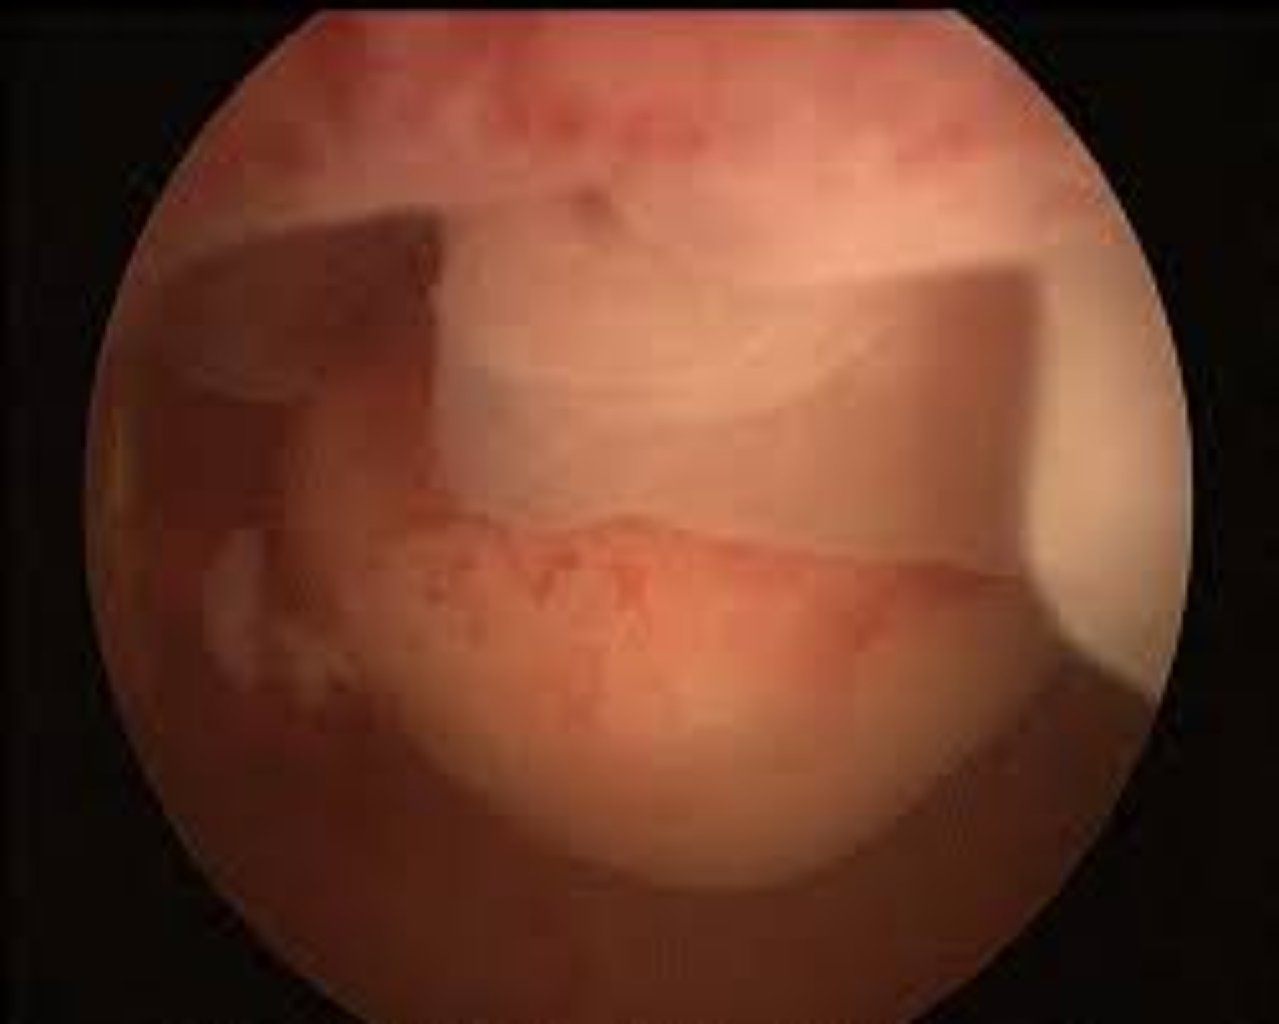

Histeroskopiya necə aparılır? Histeroskopiya zamanı həkim vajinadan uterusa histeroskop adlanan n ...